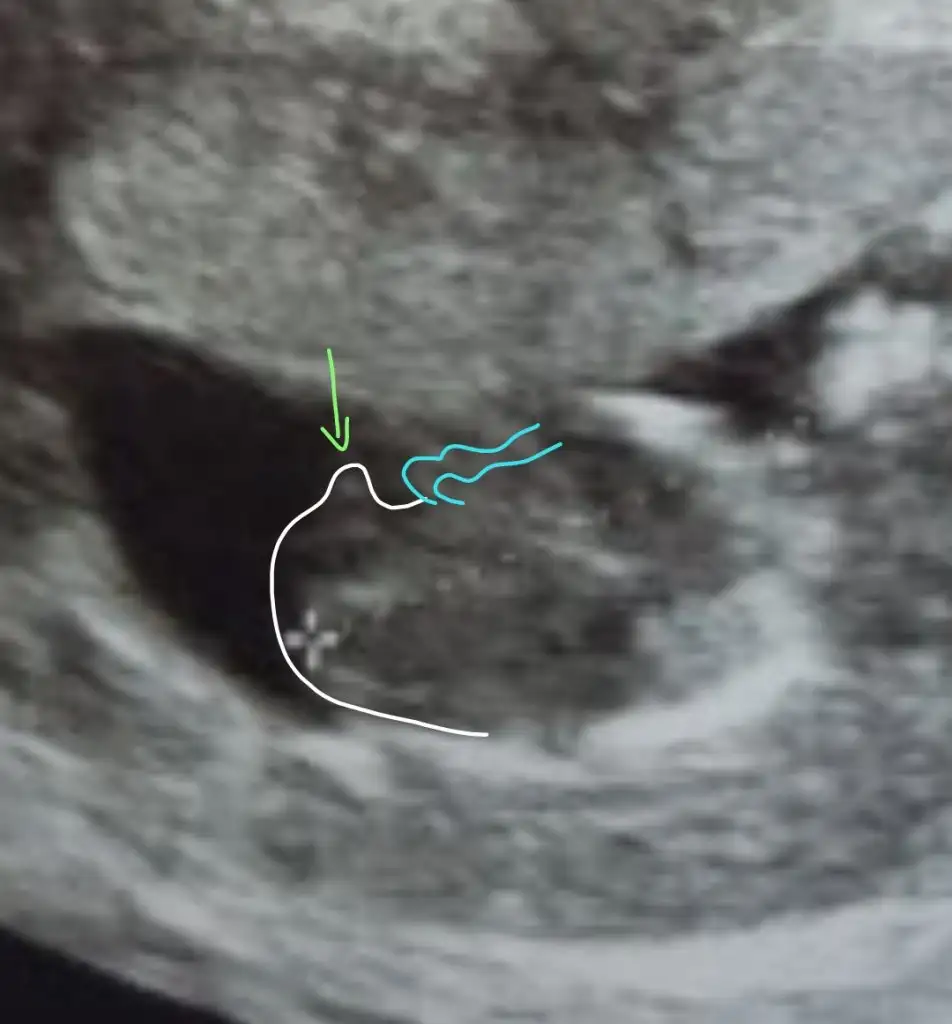

Karından baktı ise kız vajinal ise erkek en iyi 11 12 13 haftalar olmalı

Ikra meyra cıgim.. bizim çıkıntı paralel gorunmuyor mu. Kız gibi olmasin sanki. Aslinda ben çikınti da goremedim de

Aaa siz cizince fark ettim ya. Ne kadar bilgilisiniz hayran kaldim